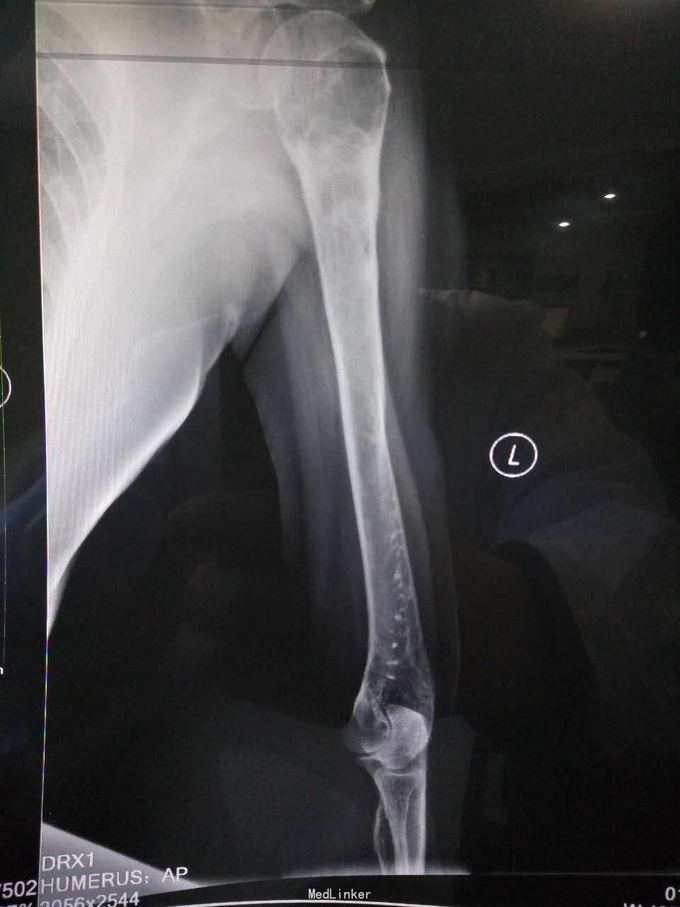

主诉:摔伤致左髋部疼痛及活动受限1小时; 病史:1小时前患者不慎摔伤,致左款疼痛,活动受限。无开放性伤口。患者半年前于华西诊断重度骨质疏松症,长期注射鲑降钙素,密固达一次。

查体,左下肢外旋畸形,髋部压痛,轴向叩击痛。 x片提示:左股骨颈、转子间骨折,左股骨耻骨上支,耻骨联合、下肢粉碎性骨折。

诊断:左股骨颈、转子间粉碎性骨折,左耻骨上支、耻骨联合、下支粉碎性骨折,重度骨质疏松症, 处理:患肢制动,牵引,注射鲑降钙素,科室讨论意见为行髋关节置换术,与换方沟通后,换方表示拒绝手术治疗,主动出院。